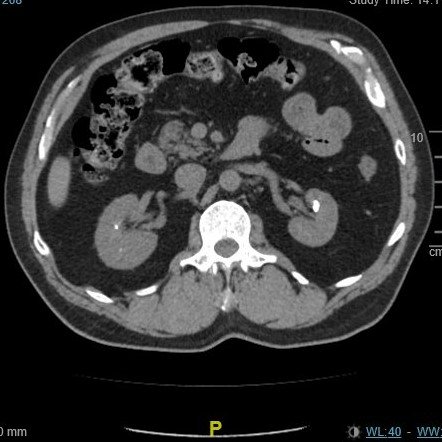

A Pain in the… Side?